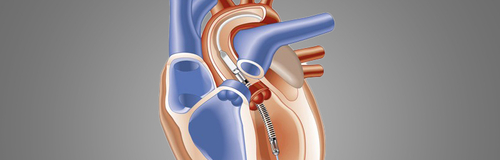

Baylor Scott & White – Fort Worth builds upon advanced heart failure program with mechanical device support

Baylor Scott & White All Saints Medical Center – Fort Worth now offers comprehensive care for patients with advanced heart failure.